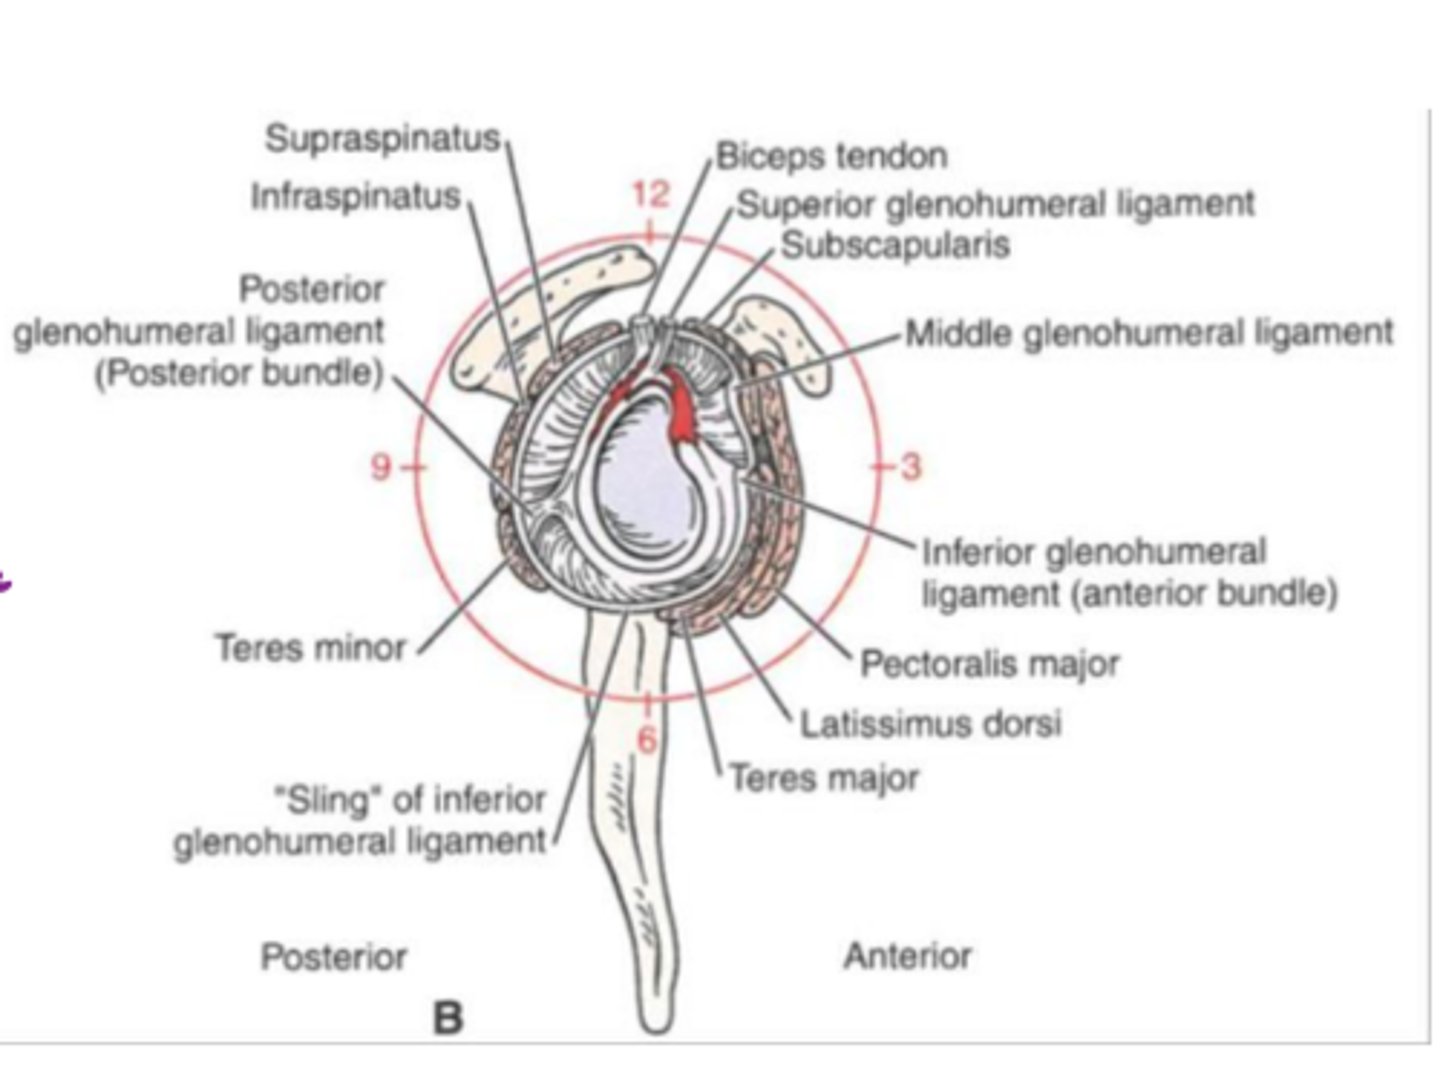

Normal superior and inferior glenoid labra without sub-labral leak of contrast material.

What does image A show?

Superior labrum (curved arrow) shows normal relationship to biceps tendon (straight arrows).

What does image B show?